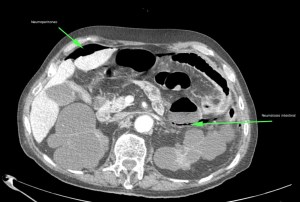

Paciente con diarrea y vómitos y dolor abdominal intenso. Antecedentes de fibrilación auricular. Analítica con discreta leucocitosis.

Se sospecha Isquemia intestinal. Veamos las pruebas complementarias de imagen:

En conclusión, estamos ante un cuadro de posible isquemia intestinal perforada, de ahí el neumoperitoneo.